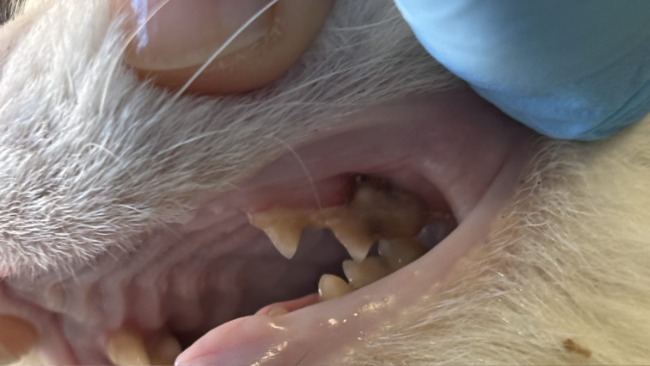

W trakcie kolejnych wizyt u weterynarza, podawanie kroplówek, leków, dalszej diagnostyki przyszedł czas na porządek w "paszczy". Trzeba usunąć kilka ząbków, zdjąć z pozostałych kamień nazębny , przepłukać dziąsła.

Dobrze ze Koleżka jest bardzo spokojnym i grzecznym kotkiem i swojej opiekunce Ani pozwala wykonywać wszystkie zabiegi .